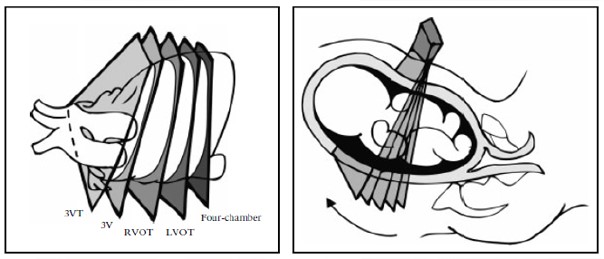

Рисунок 4. Техника сканирования сердца плода. Четырехкамерный вид получается при проведении серии поперечных срезов вдоль грудной клетки плода. Направление датчика под углом к головке плода из четырехкамерного среза дает последовательно визуализацию выходных трактов: LVOT- левый выходной тракт, RVOT- правый выходной тракт; 3V- срез через три сосуда и 3VT-срез через три сосуда и трахею.

Были описаны и другие способы оценки выходных трактов: ротационная техника [41] (Приложение S2, План 1). Из проекции четырех камер сердца сначала датчик должен быть развернут к правому плечу плода. Эта техника выполняется легче, когда межжелудочковая перегородка перпендикулярна по отношению к ультразвуковому лучу.

Она требует немного больше УЗ навыков, но обеспечивает оптимальную визуализацию выходного тракта левого желудочка, и особенно целостность выхода аорты и межжелудочковой перегородки. Это также позволяет визуализировать всю восходящую аорту, в отличие от методики развертки, когда удается визуализировать только проксимальную часть аорты.

При использовании обеих методик, после выведения проекции выходного тракта левого желудочка, датчик поворачивается по направлению к головке плода, пока не выявляется легочная артерия, которая будет почти перпендикулярной по отношению к аорте. Дополнительные проекции аорты и легочной артерии можно получить путем дальнейшего продвижения или наклона датчика к головке плода от выходного тракта правого желудочка.